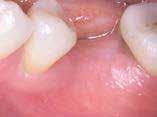

A 2020 januárjában elkezdett kezeléssorozat befejezését az év márciusában, hazánkba is begyűrűző Covid-19 pandémia késleltette, így kb. 6 hónap gyógyulás után láttunk hozzá az emergencia profil és a gingivális zenit ideiglenes koronával történő formázásához (11. és 12. kép). A 3 hetente végzett apró alakításokkal sikerült megfelelő ínyprofilt kialakítani, a „rózsaszín esztétika” a páciens számára is megfelelő volt. A bal felső nagymetsző fog meziális kompozit tömés cseréjét követően, individualizált nyitott kanalas lenyomati fejet készítettünk: az akrilát ideiglenes korona profilját átlátszó szilikonnal lemásoltuk, majd a körszimmetrikus gyári lenyomati fej és az ideiglenes korona kontúrja közötti hézagot folyékony kompozittal töltöttük ki (13. kép). Az így készített egyéni lenyomati fejjel vettünk lenyomatot a végleges, kerámialeplezésű cirkónium-dioxid vázas, átmenő csavaros rögzítésű koronához. (A fogtechnikai munkát Nébl Péter fogtechnikusmester készítette.), (14., 15., 16 és 17. képek).

A kész korona átadásakor a páciens elégedett volt az esztétikával, az azóta eltelt évben rendszeres kontrollokon jelent meg, melyek során meggyőződtünk a kemény- és lágyszövetek stabilitásáról (18. és 19. képek).